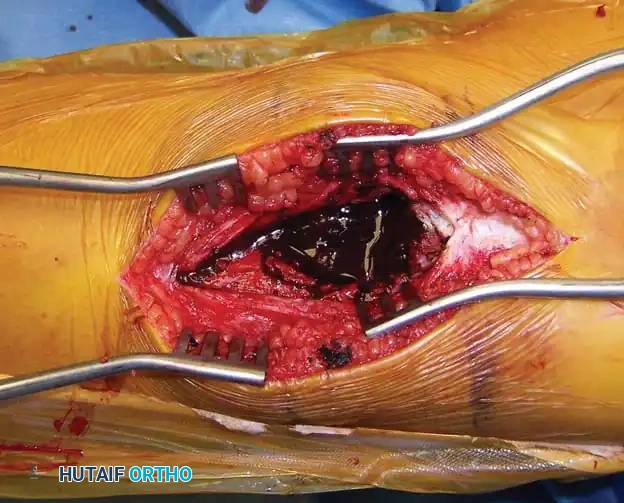

Step-by-Step Operative Technique:

- Exposure and Cortical Window: Following standard surgical approach and tourniquet inflation, the thin, reactive cortical shell is identified. A large cortical window is created to allow complete visualization of the entire cyst cavity.

- Gross Curettage: The blood-filled contents and fibrous septations are aggressively evacuated using large curettes.

Intraoperative photograph revealing the multiloculated, blood-filled cavity characteristic of an ABC.